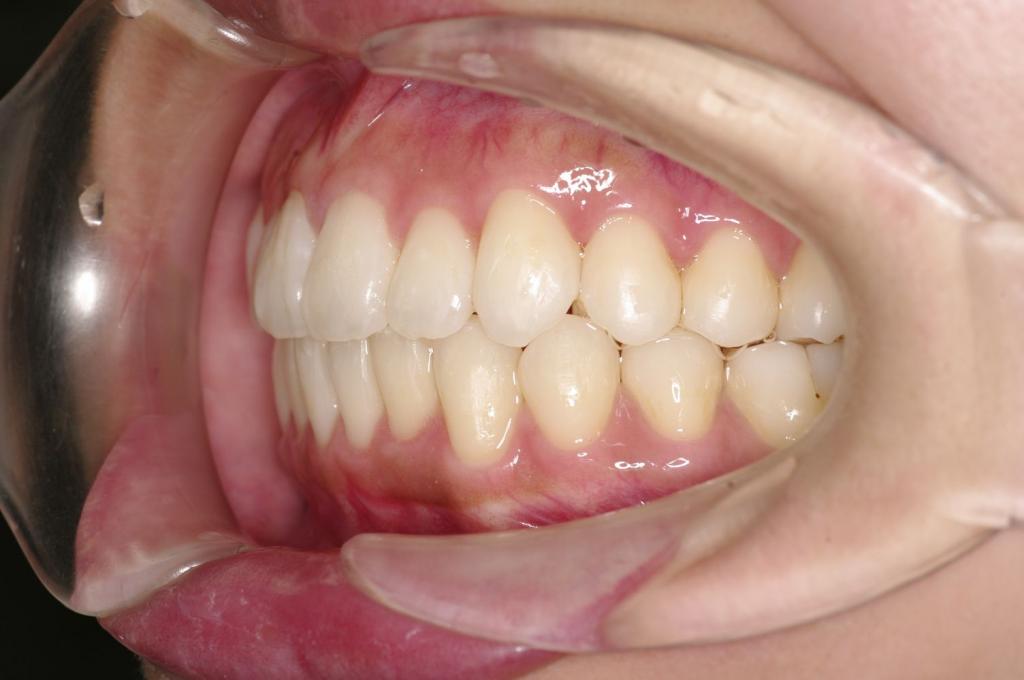

前歯、出っ歯・開咬の矯正治療

(治療期間、治療前後写真、治療方法、費用)WORKS